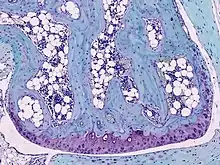

![]() Light micrograph of undecalcified hyaline cartilage showing chondrocytes and organelles, lacunae and matrix. | |